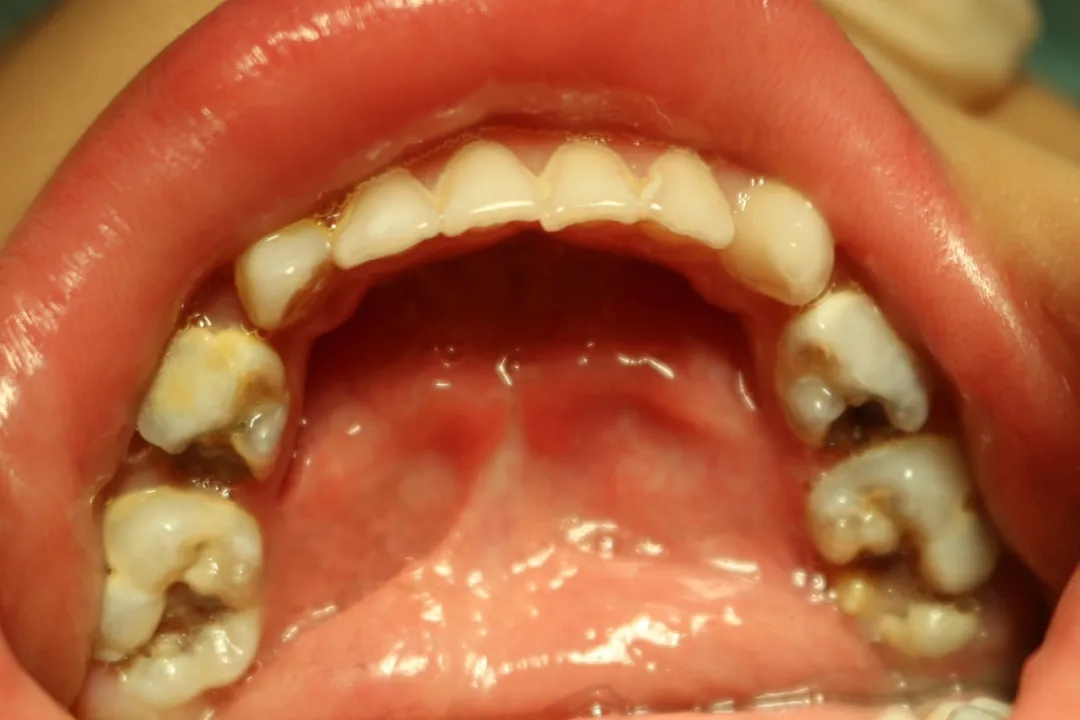

▲迪迪治疗前龋齿

三岁的迪迪(化名),一周之前还饱受牙痛的折磨。7月2日,妈妈带着迪迪从呼市来到了包医一附院口腔科就诊,据迪迪妈介绍,孩子已经牙疼一周了,吃不下饭,还总是哭闹睡不好觉。迪迪的接诊医生赵越检查后发现,迪迪的牙齿有13颗都是问题牙,包括6颗需要做根管治疗的复杂牙、7颗需要充填的牙齿。